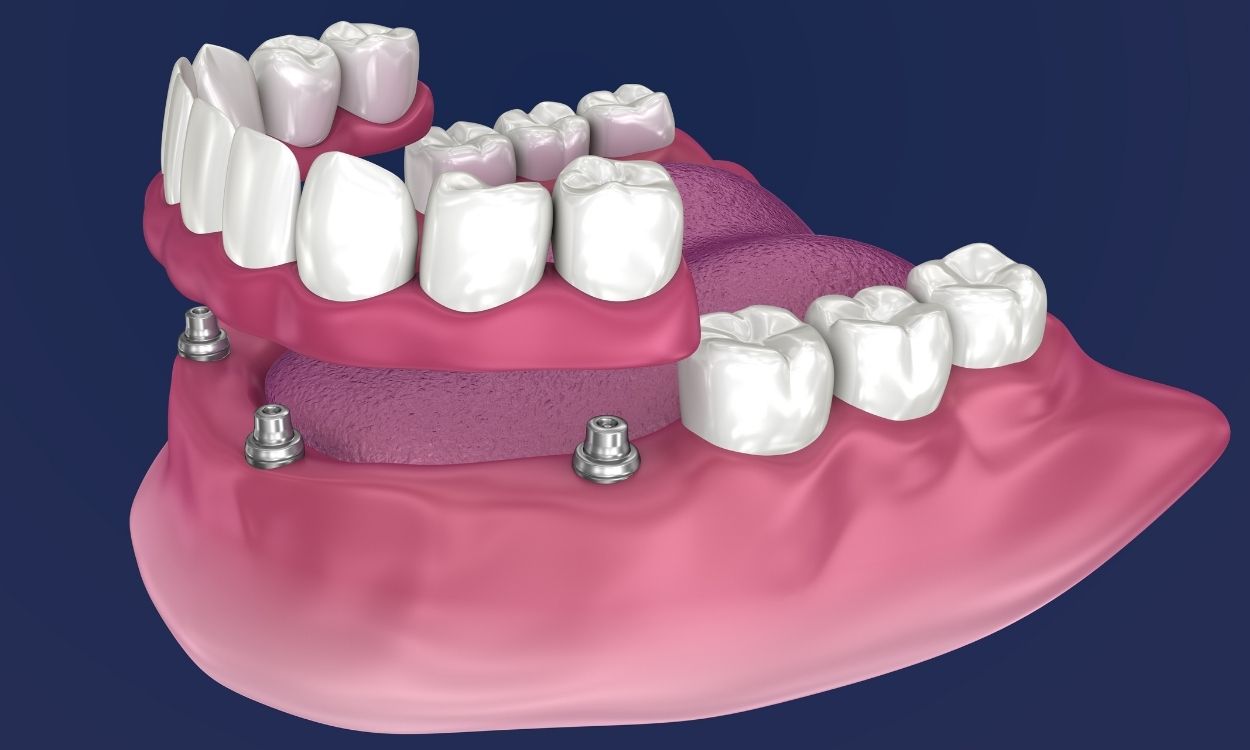

Ko ljudje prvič pregledajo cene zobnih vsadkov, se pogosto osredotočijo le na številke. Vendar pa vsadki ponujajo prednosti, ki jih druge rešitve le redko dosežejo. Za razliko od snemljivih protez so vsadki pritrjeni na svoje mesto. Pri jesti in govorjenju se čutijo naravno. Pacienti pogosto pravijo, da pozabijo, da jih sploh imajo. Ta stabilnost ščiti tudi okoliške zobe, ker se vsadki ne zanašajo na sosednje zobe za oporo. Vzdržljivost je še ena pomembna prednost. Z ustrezno ustno higieno in rednimi zobozdravstvenimi pregledi lahko vsadki zdržijo več let, včasih celo vse življenje.

Na prvi pogled se cene zobnih vsadkov morda zdijo zmedene. Ena klinika lahko ponudi določeno ceno, druga pa nekaj povsem drugega. Ta razlika je normalna, saj so vsadki zelo personalizirani tretmaji. Na končni strošek vpliva več dejavnikov. Prvi dejavnik je število potrebnih vsadkov. Zamenjava enega samega zoba zahteva drugačen pristop kot obnova celotne vrste zob. Drug dejavnik je vrsta uporabljenih materialov. Visokokakovostni vsadki so izdelani iz trpežnega titana, ki je zasnovan tako, da se naravno integrira s kostjo.